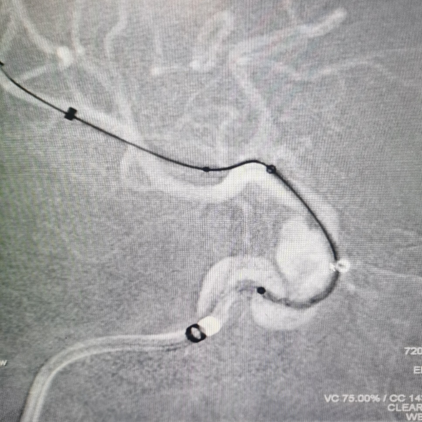

右侧颈内动脉:

Synchro 2导丝和XT-27同轴带CAT5到大脑中M1段远端

路径迂曲,海绵窦III型导致基础支撑不足,长鞘下坠,Surpass Streamline血流导向密网支架无法到位。

Infinity长鞘轻松推送至海绵窦段高到位,微导丝和CAT 5送高,增强系统支撑,支架顺利到位。